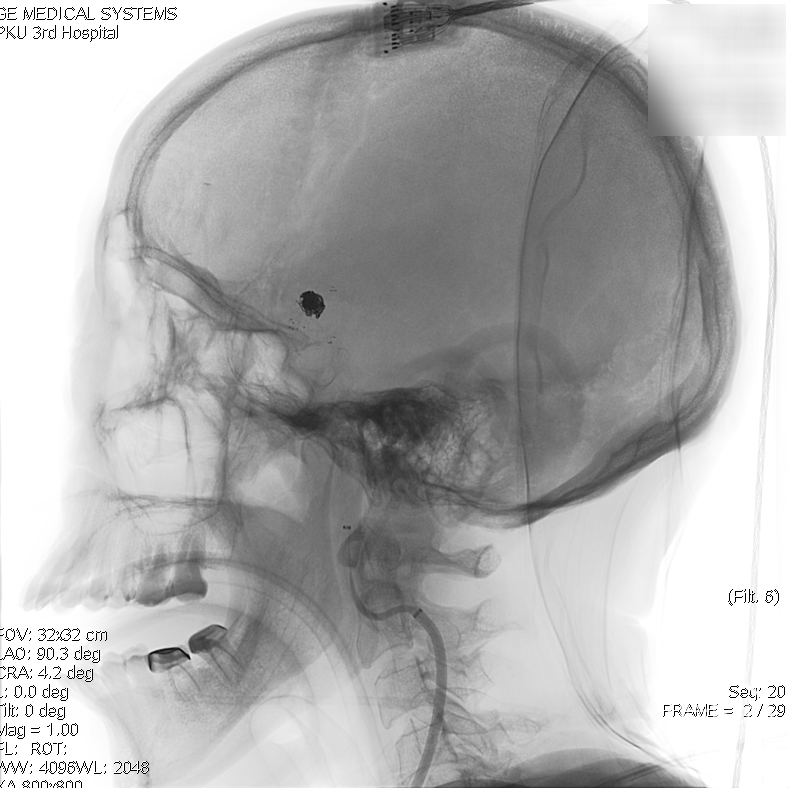

术前影像:术前正侧位。

术前影像学检查:术前正侧位。